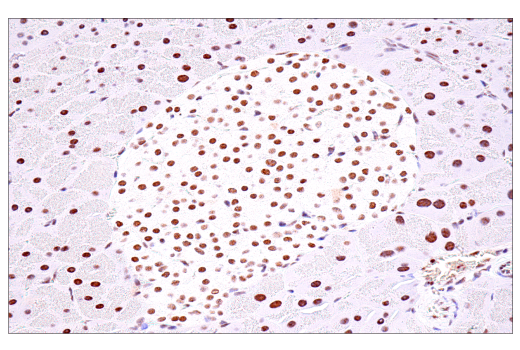

Immunohistochemical analysis of paraffin-embedded human B-cell non-Hodgkin lymphoma using USP39 (E8U2M) Rabbit mAb.

Immunohistochemistry Image 3: USP39 (E8U2M) Rabbit Monoclonal Antibody